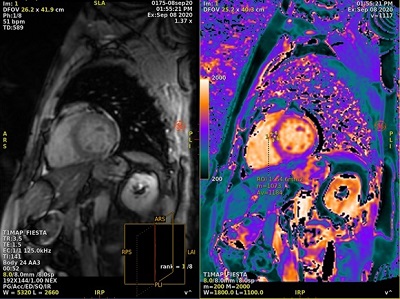

Motion Compensation with T1MAP scans

T1MAP with Motion Compensation scans provide better delineation of anterior and anteriolateral segments, which improves the accuracy of T1 estimates due to reduced motion artifacts.

For T1MAP scans, Motion Compensation corrects for small residual respiratory motion which may still be present during a breath hold scan. Therefore, acquire T1MAP scans during breath hold.

- T1MAP-SPGR with Imaging Option Motion Compensation

- T1MAP-Fiesta with Imaging Option Motion Compensation

Image reconstruction considerations

- The Motion Compensation preview images are displayed in AutoView while scanning but they are not stored in the Patient List. When displayed in AutoView, the series number is multiplied by 100. For example, if the original series is 2, the preview series, as displayed in AutoView, is 200.

Figure 5. AutoView series